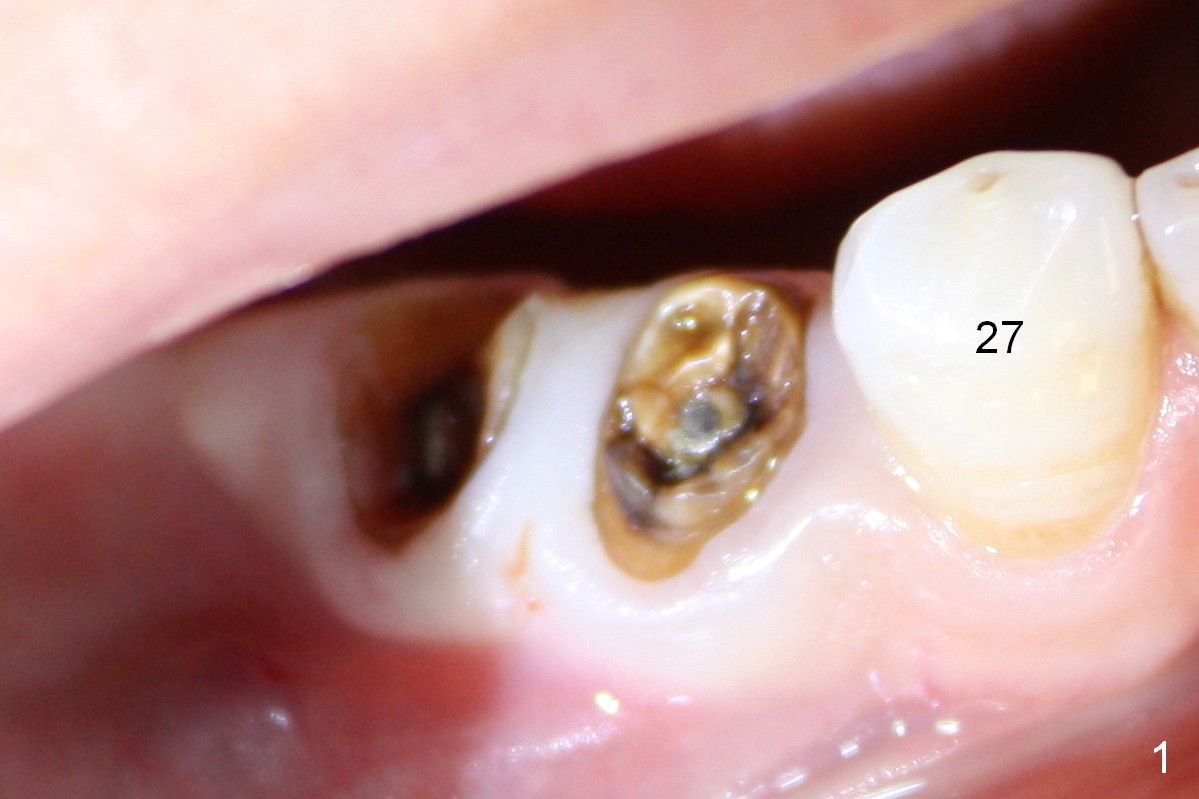

Four months and a half, the buccal margin has to be extended (Fig.3 ^). A month later, gingival recession becomes more obvious (Fig.4 ^ with exposure of the rough surface of the implant). Occlusal view demonstrates the buccal position of the implant and abutment at #29 (Fig.5). CBCT will be taken to confirm the malpositioning. If it is confirmed, the abutment and implant will be removed and un-torqued. The lingual bone will be removed; osteotomy will be also extended apically cautiously. The same or longer implant will be placed immediately. Probably two 1 piece implants will be placed at the same time at the site of #30, since the ridge is narrow.